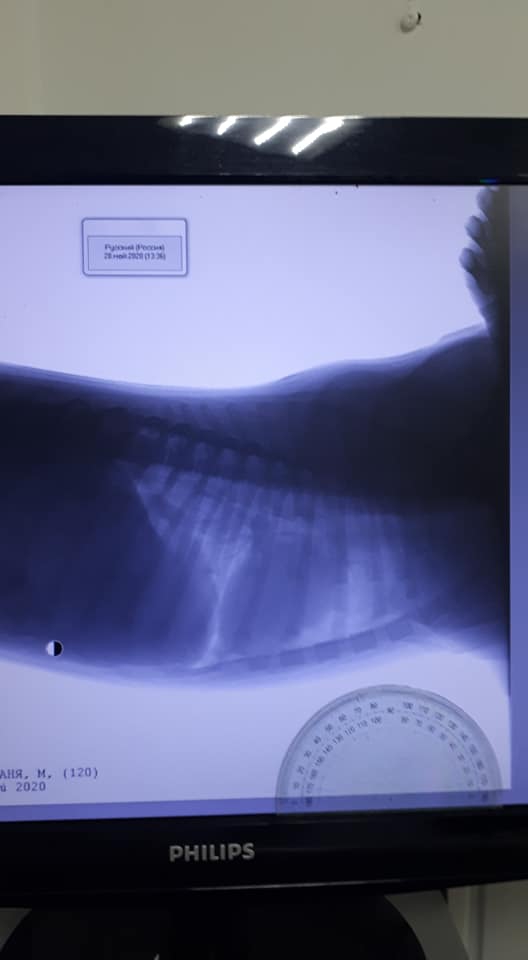

“По УЗИ пока все в норме. Рентген показал ушиб грудной клетки, — пишет Елена. — Собаку спас дождь и мокрая земля. Собачка молодая. Зубки еще молочные. Очень добрая. Сейчас будем наблюдать. Спасибо большое соседям, взяли на передержку. Соседи обещали в полиции все написать”.